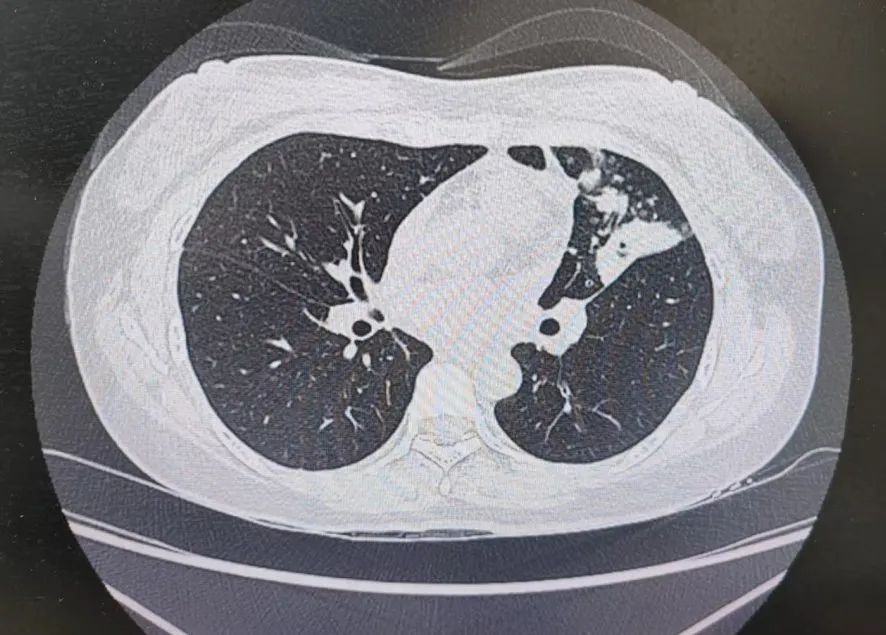

患者肺部CT影像

“一般來(lái)說(shuō),肺炎經(jīng)過(guò)一周的抗感染治療,病灶會(huì)有所吸收。但陳女士的肺部陰影紋絲不動(dòng),這種情況必須提高警惕。”宋剛主任團(tuán)隊(duì)立即啟動(dòng)了更深入的“三部精準(zhǔn)診斷”程序:

3、CT引導(dǎo)下穿刺活檢:病理診斷為左肺上葉腺癌。

肺炎型肺癌,因其影像學(xué)表現(xiàn)與普通肺炎極為相似,臨床上誤診率極高。然而確診僅是第一步。宋剛主任當(dāng)天即召集腫瘤科、病理科、影像科等多學(xué)科專家會(huì)診,為陳女士制定個(gè)體化治療方案。